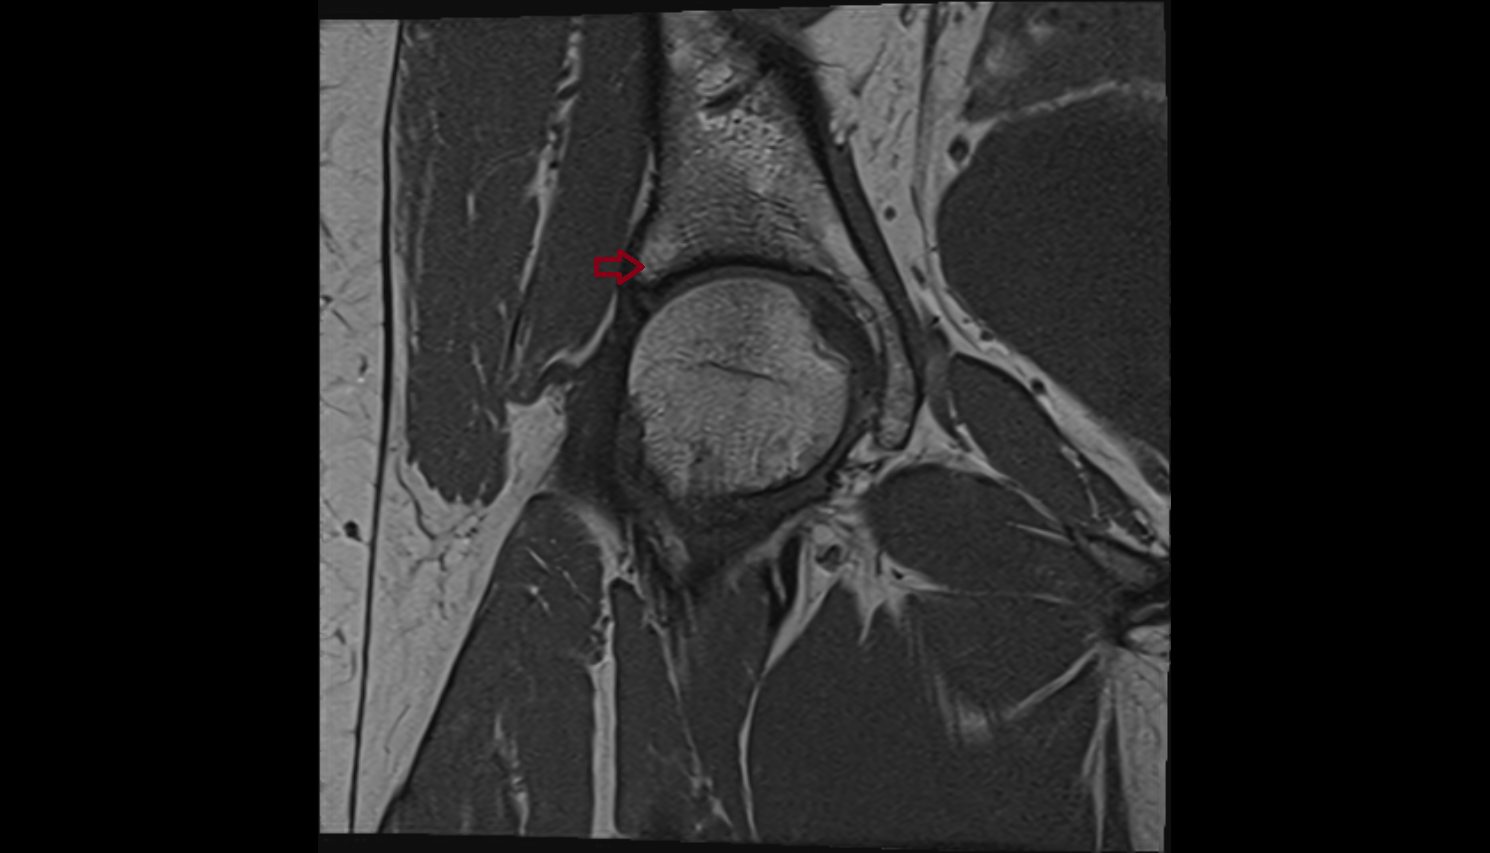

- Medial meniscus

- Lateral meniscus

- Medial collateral ligament

- Lateral collateral ligament

- Knee Joint